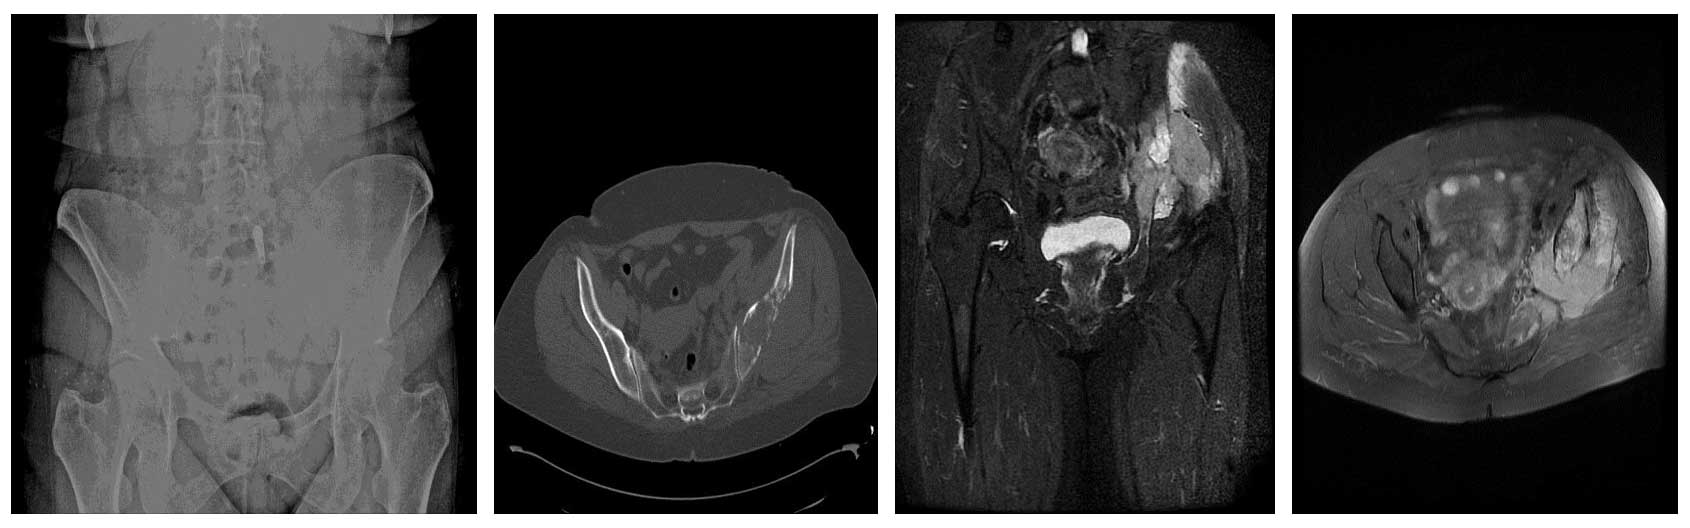

Ameliyat Öncesi: Röntgende düzensizlik, tomografide kemik harabiyeti, MR’da yumuşak doku komponenti görülmekte.